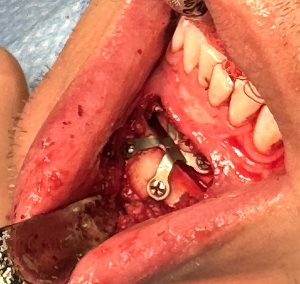

- Rigid fixation is mandatory

- Prefer new titanium plates

- Avoid reusing old screw holes when possible

- Consider dual-plate fixation for:

- Vertical lengthening

- Nonunion

- Large advancements